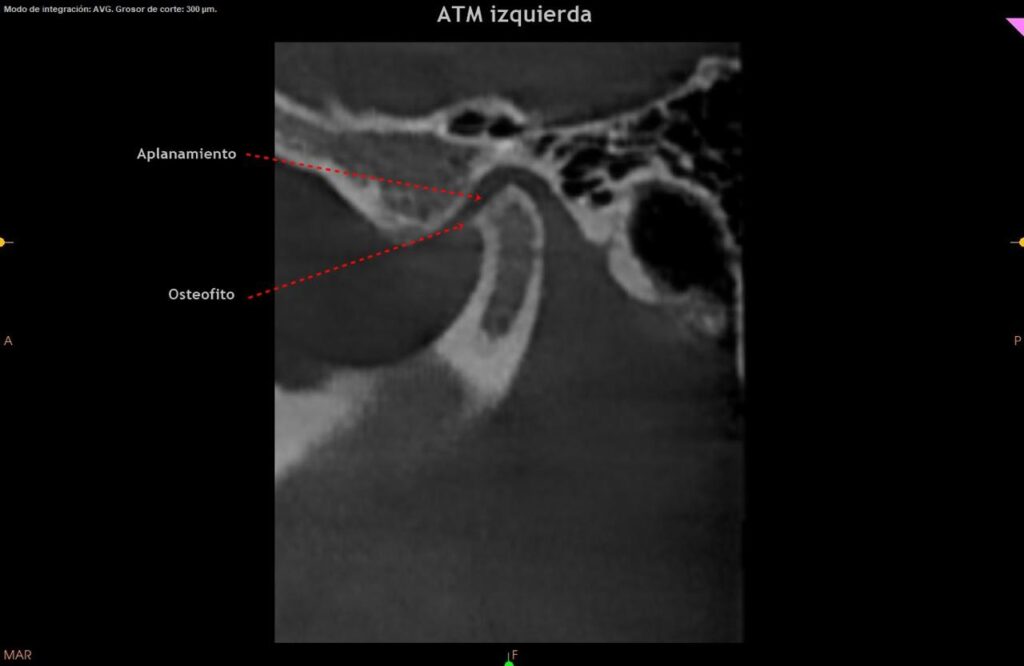

Evaluación médica y por imágenes:

Realizar una evaluación clínica completa y usar estudios de imagen (como rayos X, tomografía computarizada o resonancia magnética, para confirmar la presencia de osteofitos y evaluar su impacto en la articulación. -destacó la Dra. Mónica Souza Paz, quien está graduada de la UNAM y cuenta con un posgrado en ortodoncia y especialidad en dicho campo.